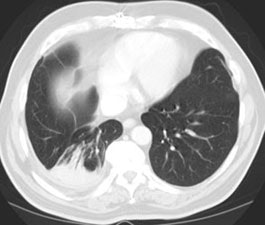

HRCT can suggest changes due to asbestosis in one third of patients with a normal CXR, however, a normal CT cannot exclude asbestosis. Abnormalities due to asbestosis are usually bilateral and somewhat symmetric. On HRCT the primary site of parenchymal involvement is the posterior, subpleural region of the lower lobes. As such, patients should be imaged in the prone position at maximal inspiration. CT findings in asbestosis include: 1- "Dot-like" opacities in the sub-pleural lung several millimeters from the pleura. This is the earliest abnormal finding recognizable on HRCT and it is due to peribronchiolar fibrosis extending to involve the contiguous airspaces and alveolar interstitium. 2- Thickened subpleural lines occur due to interlobular septal (irregular thickening), and intralobular fibrosis in the lung periphery; 3- Parenchymal bands: Non-tapering linear densities measuring 2 to 5 cm in length that contact the pleural surface are probably most commonly identified in patients with asbestos related lung disease. Multiple parenchymal bands were seen in up to 66-76% of patients and have a basal predominance. Because of their association with sites of pleural thickening, they are felt to represent the earliest stages of rounded atelectasis; 4- Honeycombing: Small, 2 to 5 mm cystic spaces with discrete thickened walls. This represents the non-specific end stage of many fibrosing conditions and it is found in nearly 100% of patients with end-stage asbestosis (2). 5- Curvilinear subpleural lines and hazy subpleural densities: Curvilinear lines are located within 1 cm of the periphery and course parallel to the chest wall. Patchy areas of increased density may be seen normally in the dependent lung, they are only abnormal when they persist in non-dependent lung. Subpleural lines have been identified in up to 40% of patients with asbestosis (however, subpleural lines have been demonstrated in 15-20% of normal patients). Although the peripheral interstitial pattern seen in asbestosis has also been described in other disorders, its demonstration in patients with a strong history of asbestos exposure offers compelling evidence for the diagnosis of asbestosis. Ground-glass opacity is uncommon in patients with asbestosis.

Round atelectasis on PET FDG imaging: The images below demonstrate the typical CT and FDG PET findings in round atelectasis. On CT, there are thickened lung markings and vessels which swirl into the lesion that abuts an area of pleural thickening. Note the lack of metabolic activity in round atelectasis on PET imaging. |